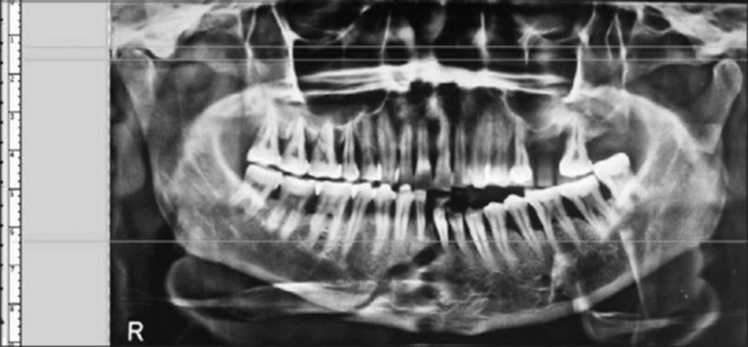

Parameters of maximal interincisal mouth opening and protrusive movements were measured from the incisal edges of the upper and lower anterior teeth while lateral movements and deviation of the mandible on mouth opening were assessed and measured with reference to the dental midline using a metallic scale. All the above parameters were assessed preoperatively and at an interval of day 3 and weeks 1, 2, 4, and 6 postoperatively for the surgical group. For the conservative group, parameters were assessed and measured preoperatively with follow-up at an interval of 2, 4, and 6 weeks postoperatively. The pain was measured using the visual analog scale (VAS) [Figure 1] based on the patient perception of pain preoperatively and at an interval of day 1, day 3, and weeks 1, 2, 4, and 6 postoperatively for both surgical and conservative groups. The height of the ascending ramus was measured on the OPG from the superior-most point of condyle to the inferior-most point of the angle of the mandible on the affected side radiographically using the ADOBE Photoshop software preoperatively and at an interval of day 3 and 6 weeks postoperatively for both surgical and conservative groups. In addition, the degree of displacement of the condyle was assessed and measured using cone-beam CT for every case to be selected for the study.

Figure 3: Measurement of the height of ramus using orthopantomograph with Adobe Photoshop software